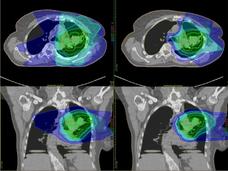

Is Proton Therapy Safer than Traditional Radiation?

Some experts believe that proton therapy is safer than traditional radiation, but research has been limited. A new observational study compared the safety and effectiveness of proton therapy and traditional radiation in adults with advanced cancer.